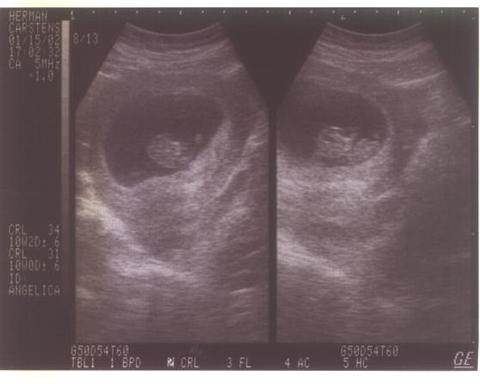

Aqui van

mis primeras fotitos... que

las disfruten...

|

9

Semanitas |